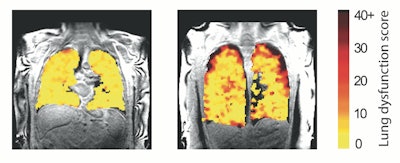

Lung function MRI showing problem areas (measurement levels of dysfunction) in lung transplant recipients.Image and caption courtesy of Newcastle University in Newcastle on Tyne, U.K.

"In those with chronic rejection, the scans showed poorer movement of air to the edges of the lungs, most likely due to damage in the very small breathing tubes (airways) in the lung," they wrote.